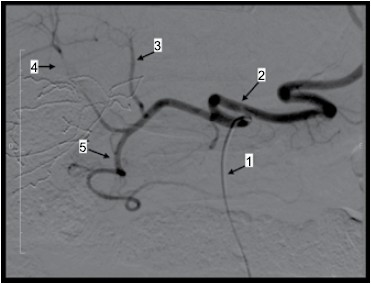

Observe a imagem.

Considere o exame angiográfico apresentado e assinale a alternativa correta.